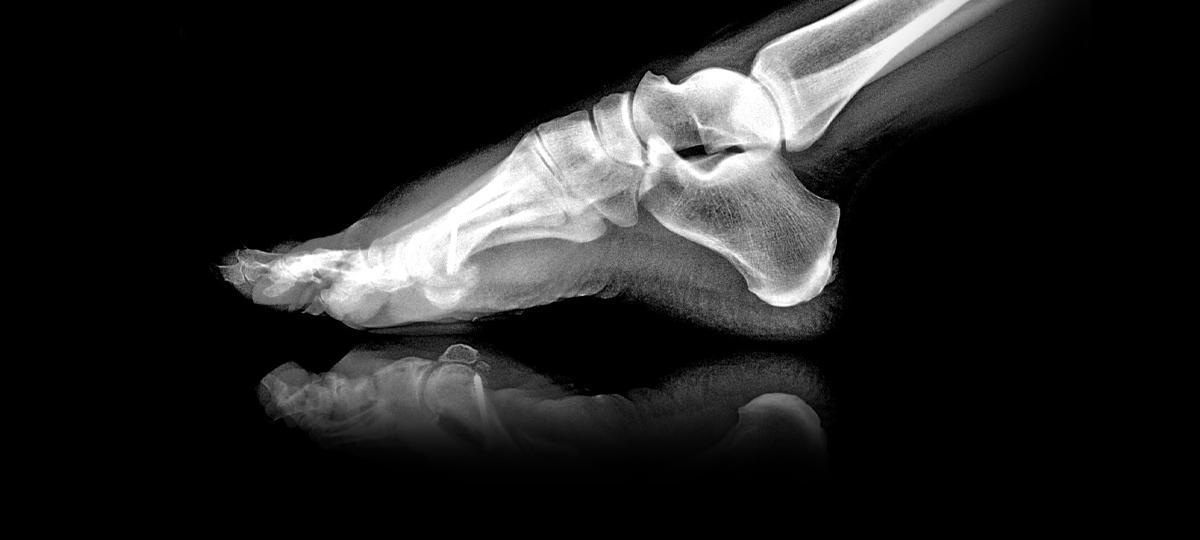

23.02.2019 14:21 Фото носит иллюстративный характер. Источник фото

Во время гололеда я упала на тротуаре у своего дома, поскольку дорожка не была посыпана песком. В результате падения получила закрытый перелом голени. Могу ли я предъявить к ЖСПК претензии материального характера в связи с полученной травмой? (Елена, Брест)